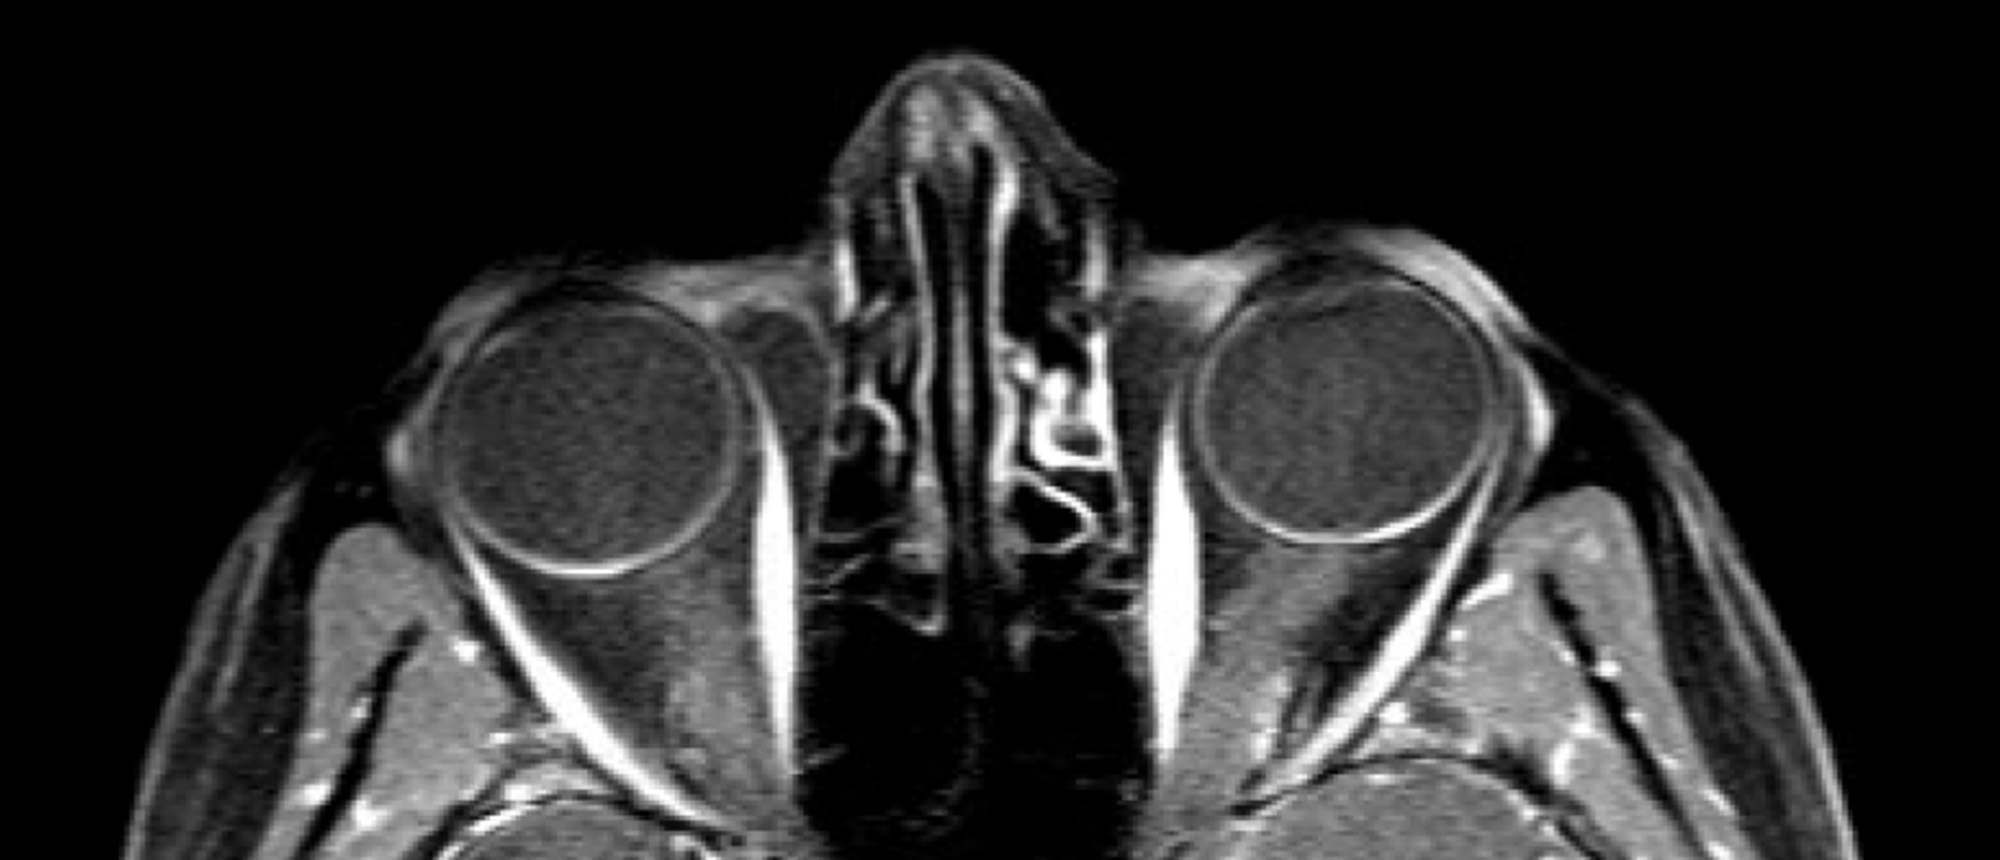

Peripapillary Intrachoroidal Cavitation A patient presented to the neuro-ophthalmology clinic after referral from his primary retina physician for further evaluation of a point of light seen in his left eye. The patient had no significant past medical history, but had a past ocular history of patho…